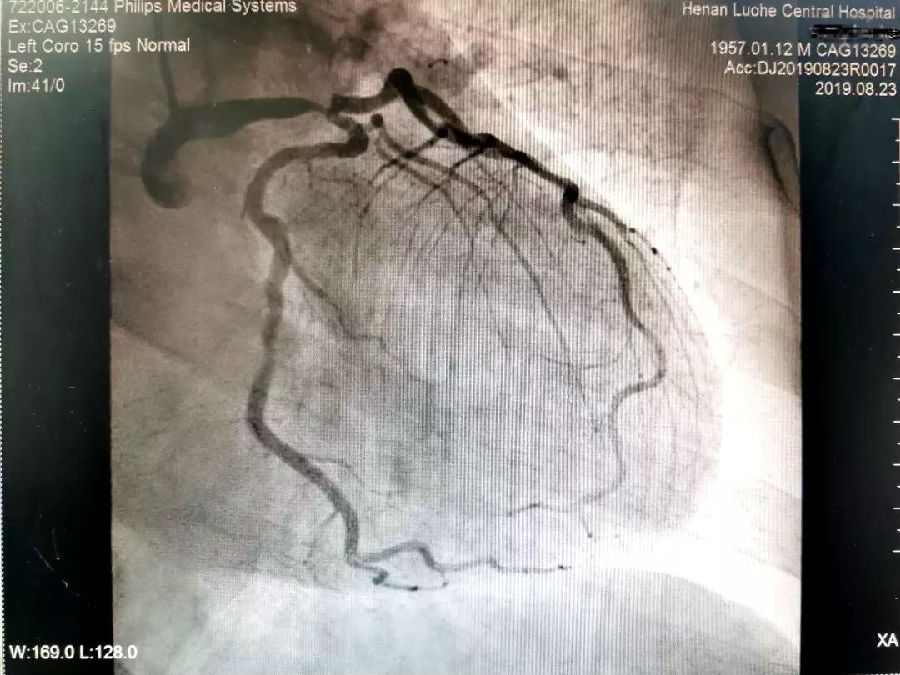

▲术前造影显示左主干病变

“一般冠心病患者,若血管严重狭窄或堵塞,可采取支架植入的方法即可缓解胸痛等症状;但王大爷是左主干加三支血管病变,同时合并糖尿病,不适合放支架。”漯河市中心医院副院长、心内科学科带头人刘东亮,迅速召集医务科、心胸外科、重症监护室、麻醉科、体外循环科、心脏康复中心、营养科等科室专家进行联合会诊。多学科专家很快达成一致意见:为患者实施不停跳冠脉搭桥术!